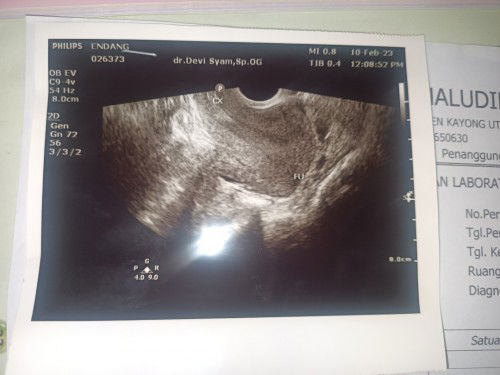

Hamil 6 Minggu apakah wajar kntung janin belum ada,,dan hny penebalan Dan sy juga mengeluarkan drh

hallo bun. 6 minggu itu dihitung dari HPHT kah? apa siklus haid bunda super teratur? klo tidak, bisa sangat wajar belum ada kantong nya bun. karena bisa saja usia kandungan sebenarnya belum 6 minggu. aku dlu klo dr HPHT harusnya sudah 9 minggu, tapi dari USG baru 5 minggu. ternyata karena siklus aku tdk teratur, alhamdulillah anaknya sudah lahir dengan sehat sekarang.

aku dulu 9w masih kantong bun segini, trs usianya kalo dilihat dr hasil usg mundur jd 5w, diresepin penguat kandungan, selama hamil syukur gk ada keluhan, flek dll walaupun diawal kayak ga wajar masa 9w masih kantong, tp skrng udah masuk 38w dari hpht, berhubung kamu ada keluhan mengeluarkan darah jadi ya nggak wajar bun, kata dokter gimana bun diresepin penguat kandungan atau nggak? semoga baik² saja